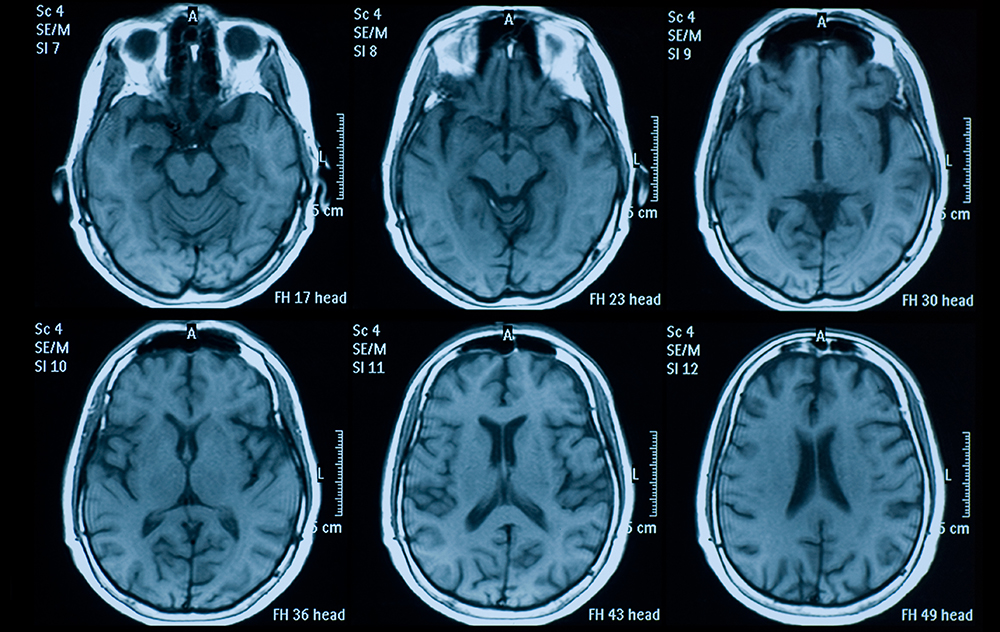

Brain MRI

If you look closely at the brain of a person suffering from Alzheimer’s or dementia, you can see the differences. Structurally, there is atrophy—shrinking in the cerebral cortex and hippocampus—and enlarged ventricles.

Doctors don’t diagnose Alzheimer’s or dementia solely through MRIs. There are tests and assessments, but the scan is a part of the puzzle that can help greatly in diagnosis and treatment.

Typically, ASD is diagnosed by a therapist because it’s very behaviorally driven. The therapist goes through a list of behaviors or difficulties a patient might be exhibiting and makes a diagnosis. With neuroimaging, we’re trying to see if we can come up with a brain-based understanding of ASD in addition to the behavioral one made by the therapist. Essentially, we’re taking a thousand fMRI brain scans—which measure brain activity by detecting changes associated with blood flow—and using high-performance computing available at SCU (WAVE) to analyze the correlations of brain networks.